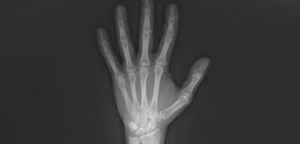

Uma dessas aplicações é a utilização da prata na Radiologia. Todo mundo já fez, ou conhece alguém que fez, o exame de radiografia, que é uma técnica de exame de imagem que utiliza raios X para ver um material cuja composição não é uniforme como o corpo humano. Mas onde que a prata entra nessa história?

Figura 1. Exame radiográfico de uma mão. A imagem formada só é possível graças à prata metálica presente no filme.